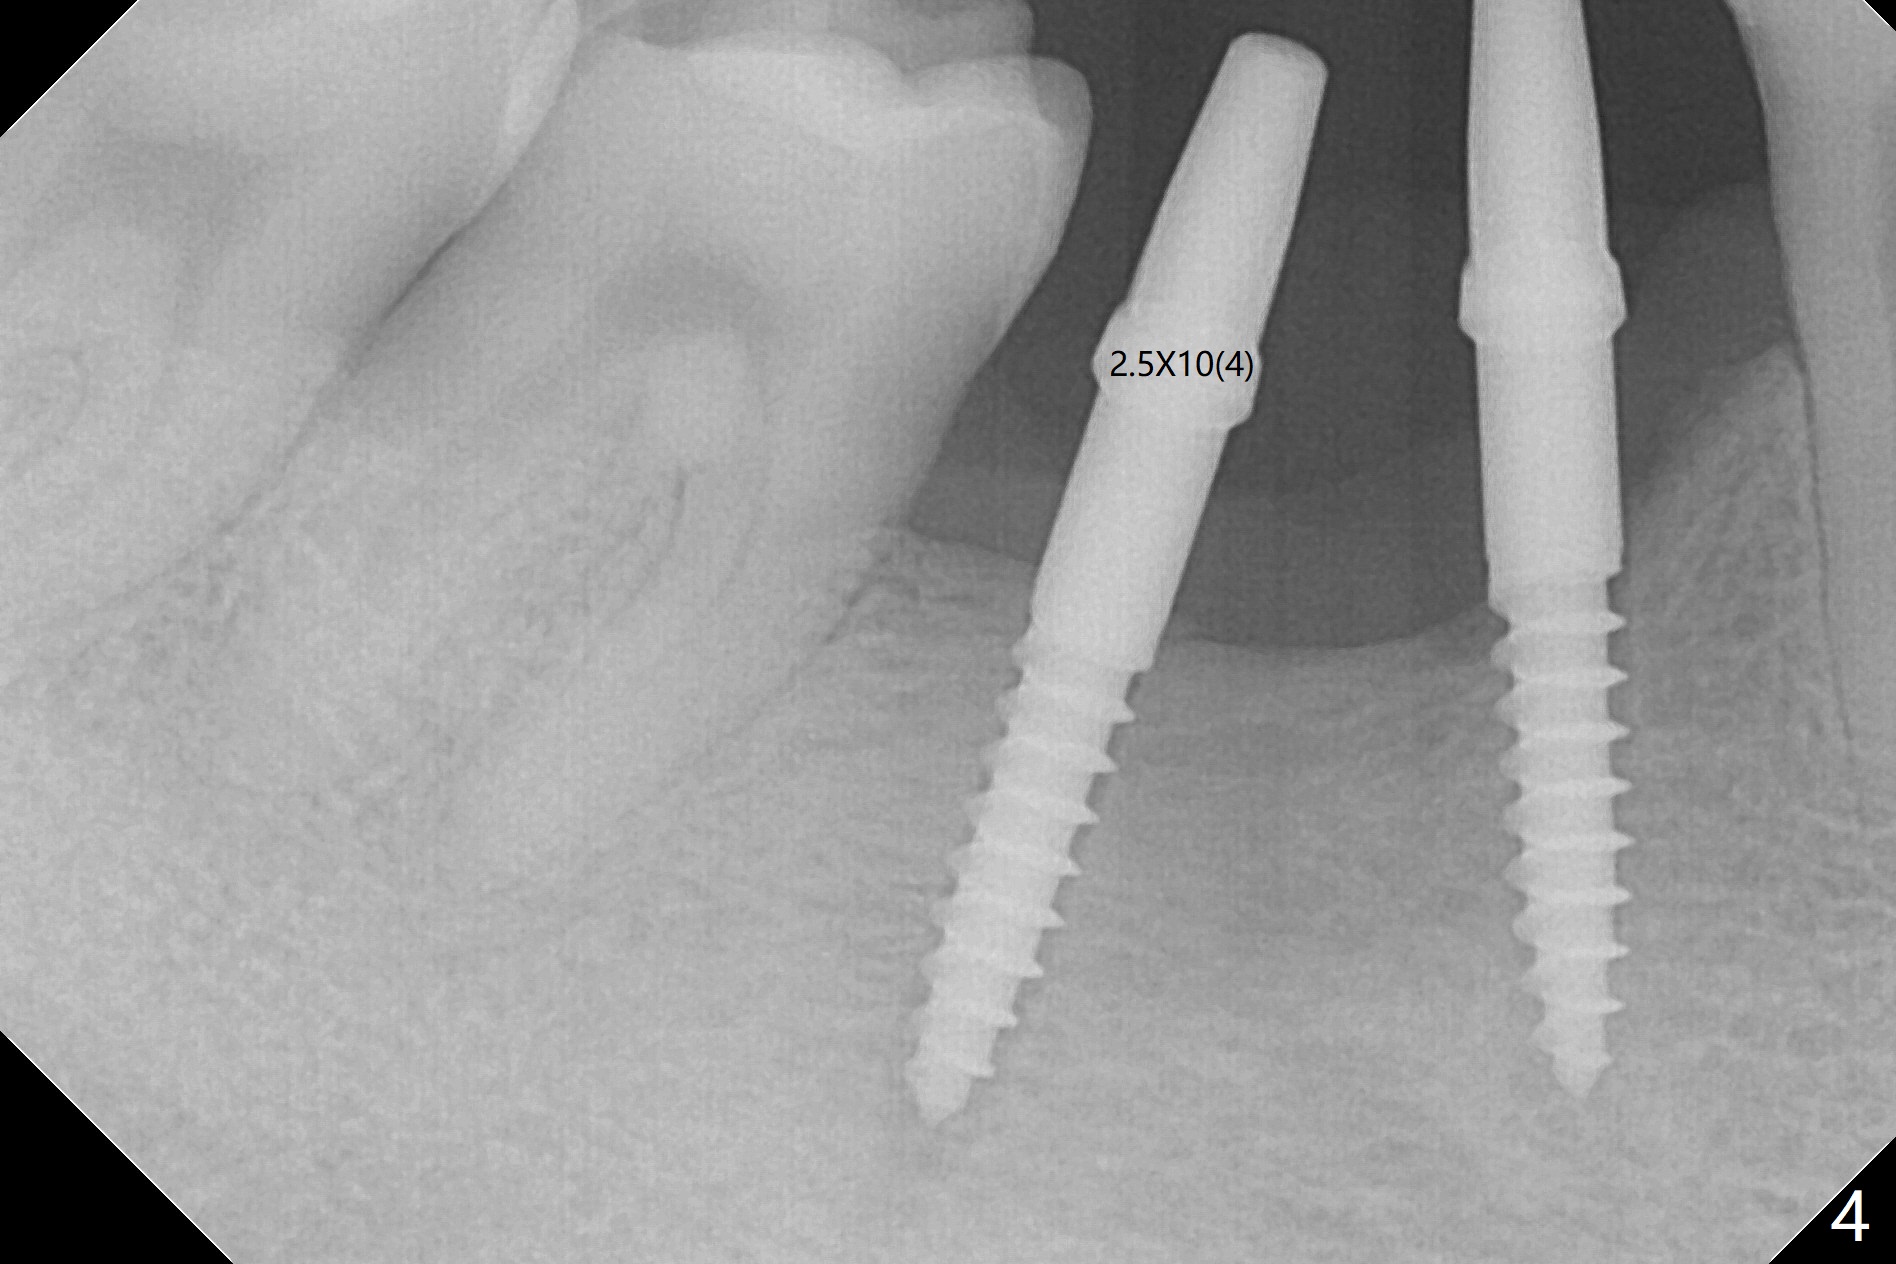

After initial osteotomy using 2.2 mm drill for 10 and 11.5 mm at #29 and 30, respectively, the guide is removed for re-insertion of drills and PA (Fig.1). The osteotomy at #29 is found lingually and in the nonkeratinized gingiva with mild laceration (wish incision to be made before osteotomy); the osteotomy is established a little lingual at #29 (Fig.2) and more or less in the middle of the narrow ridge and #30 (Fig.3). Lindamann bur is used to move #29 osteotomy buccally. A 1.5 mm drill is used to increase the depth free hand before placement of 2.5x10(4) mm 1-piece implants (Fig.4). After adjustment of the implant depth (Fig.5), CT is retaken, which shows proper implant placement (Fig.6,7). Probably due to good oral hygiene, the gingiva around the implants appears to be keratinized 4 months postop (Fig.8). After abutment preparation for margin and parallelism, impression is taken (Fig.9). When the permanent crowns are temporarily cemented, the large gingival embrasure is noted (Fig.10,11). The latter could be reduced by modifying the provisional in the healing stage. In fact the crown at #29 dislodges 2 days post cementation because lingual (Fig.12) and distal (Fig.13) placement. A surgical stent should have been fabricated from RPD for free hand placement!